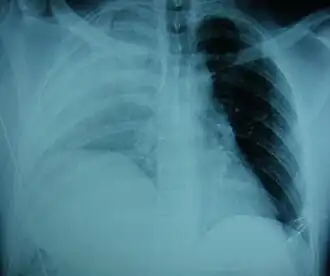

| Uma radiografia mostrando um diafragma elevado à direita[1] | |

Exames físicos não são confiáveis, pois geralmente não há sinais físicos específicos para diagnosticar essa condição.[3] Métodos toracoscópicos e laparoscópicos podem ser precisos.[12] A radiografia de tórax é conhecida por ser pouco confiável no diagnóstico de ruptura do diafragma;[4] ela apresenta baixa sensibilidade e especificidade para a lesão.[5] Frequentemente, outra lesão, como contusão pulmonar, mascara a lesão na radiografia.[6] Em metade dos casos, as radiografias iniciais são normais; na maioria dos casos anormais, há hemotórax ou pneumotórax.[4] Uma sonda nasogástrica do estômago pode aparecer na cavidade torácica na radiografia; esse sinal é patognomônico [en] para ruptura do diafragma, mas é raro.[4] A radiografia é mais eficaz para detectar a lesão quando realizada de trás com o paciente em pé, mas isso geralmente não é possível, pois o paciente costuma estar instável; assim, é feita de frente com o paciente deitado.[5] A ventilação com pressão positiva ajuda a impedir a herniação dos órgãos abdominais para a cavidade torácica, mas também pode dificultar a detecção da lesão na radiografia.[4]